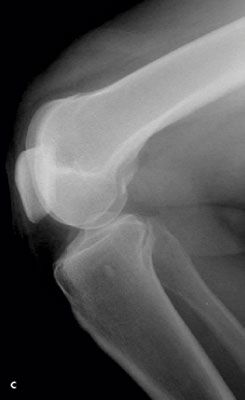

Knee pain following a soccer injury:The frontal radiograph revealsthat the patella is dislocated laterally(A). This is confirmed on the sunriseradiograph (B). A lateral radiographshows the malalignment of the patellawith the distal femur (C). Mostimportant, it also shows no fracture.Lateral dislocation of the patella isdiagnosed.